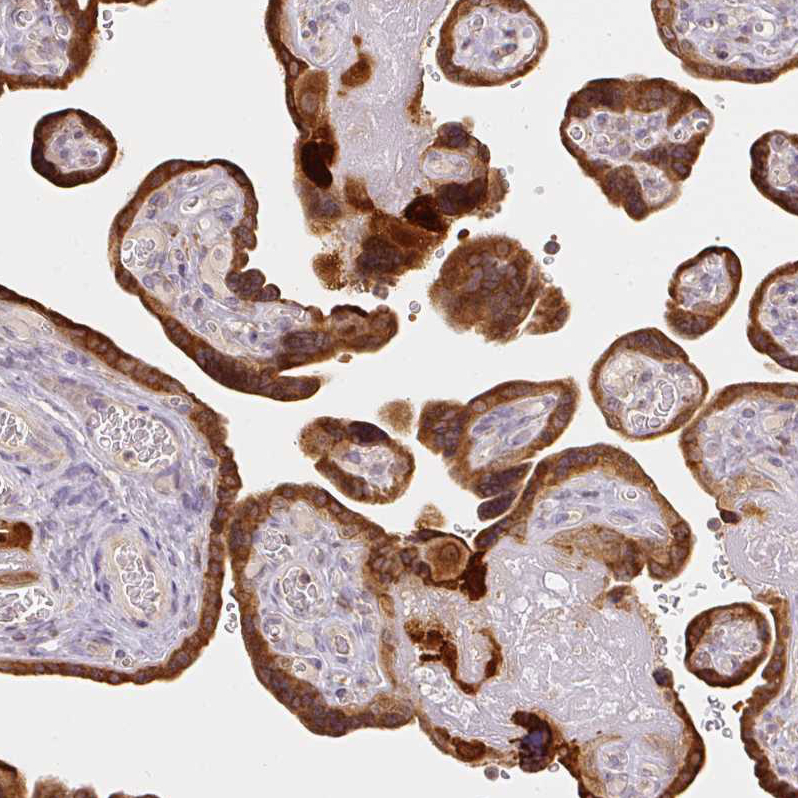

Immunohistochemical staining of human placenta shows strong cytoplasmic positivity in trophoblastic cells.